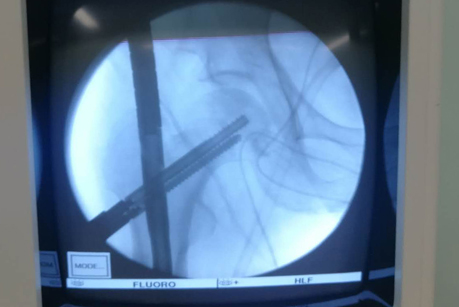

术中影像

在手术之前,首先做股骨全长薄层扫描CT,将患者股骨影像及数据搜集并记录下来,通过3D打印技术制作出一个1:1比例的股骨“复制品”,它的直径、长短、髓腔形态都与患者真实情况完全相符,甚至患者骨骼上每一块凹陷与凸起,每一点纹理和痕迹都呈现得一清二楚。然后通过在体外对模型进行模拟手术操作,准确制订出了髓内钉的入针点、长度、直径,精确计划出远端锁钉准确位置。手术时,按着术前的设计顺利完成了手术,大大缩短了手术时间,减少了对患者的创伤。术后影像骨折解剖复位,锁钉位置精准无误,术后患者顺利康复。